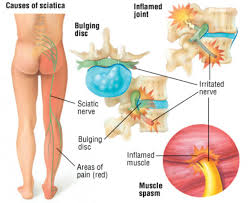

Download Sciatic nerve pain pictures